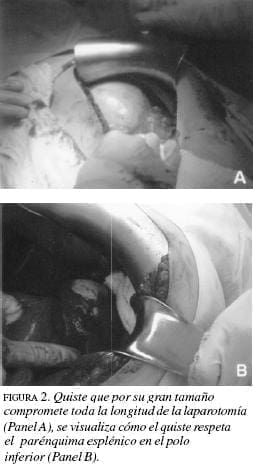

La tomografía de abdomen (figura 1A) muestra un bazo de 18 cm y lesión quística de 11X10 cm. Se practica laparotomía (figura 2A) y se realiza esplenectomía total donde se encuentra el bazo de 1420 g con gran quiste de 15X13 cm, el cual compromete el hilio (figura 3A). En el posoperatorio presenta episodio de obstrucción intestinal que requiere laparotomía. Por nuevo episodio de obstrucción intestinal parcial a los 16 meses, se realiza tránsito intestinal cuyo resultado es normal y tomografía de abdomen encontrándose alteración en estructuras vasculares portales y suprahepáticas.

En la ecografía de abdomen se encuentra un bazo de 11 cm y quiste esplénico de 6X5 cm. La tomografía de abdomen (figura 1B) confirma la presencia de un quiste de este tamaño que compromete el polo superior del bazo. Se le practica laparotomía (figura 2B) con esplentectomía parcial (figura 3B). La evolución posoperatoria es buena.